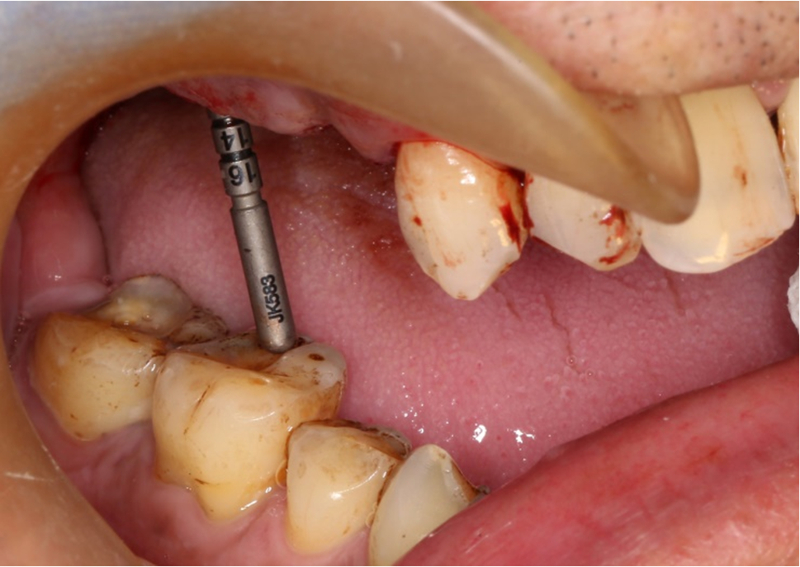

®按照術前方案進行備洞及植體植入

®按照術前方案進行備洞及植體植入,醫(yī)生可以通過屏幕軟件引導對手術中植入點、角度、深度實時追蹤

®對植體深度及方向進行確認

®完成3顆植體的植入,植體位點如術前方案設計,均在同軸線。